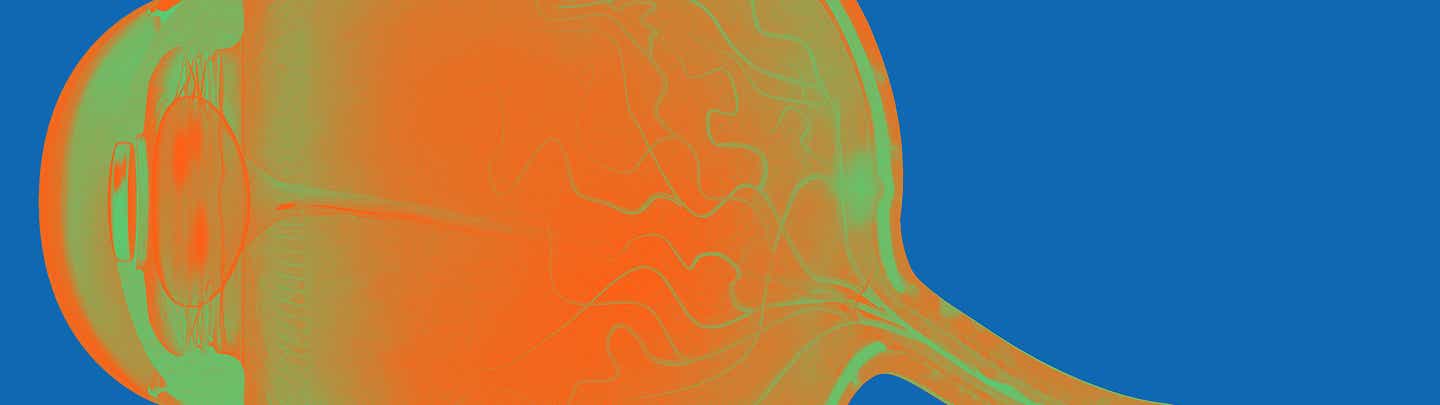

Johnson & Johnson widmet sich einem neuen Forschungsbereich mit dem Ziel, bahnbrechende Therapien zu entwickeln, die das Sehvermögen von Patient:innen mit erblichen Netzhauterkrankungen, die zur Erblindung führen können, erhalten oder wiederherstellen. Bei der spezifischen Ophthalmologie konzentriert sich das globale Team auf die Retinitis pigmentosa, eine Gruppe genetisch bedingter Netzhauterkrankungen.

Weltweit sind etwa drei Millionen Menschen von dieser seltenen Erkrankung betroffen.1 Im Zentrum der Forschungsaktivitäten stehen neben einer Gentherapie eine Vielzahl von therapeutischen Plattformen, von der topischen Behandlung über die systemische Therapie bis hin zu intravitrealen Injektionen bei häufigeren Netzhauterkrankungen.